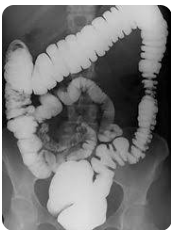

Figura 1: Enema opaco em duplo contraste mostrando haustrações normais e boa distensão do cólon. Fonte: Radiopaedia

O enema opaco, também conhecido como barium enema, é um exame radiológico contrastado utilizado para avaliar a anatomia, contorno e mucosa do intestino grosso (cólon e reto). É especialmente útil no diagnóstico de neoplasias, doenças inflamatórias, obstruções e alterações funcionais.

Pode ser realizado na técnica de duplo contraste (bário + ar) ou contraste único (apenas bário), sendo a primeira a mais utilizada devido à superioridade na visualização da mucosa.